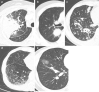

Methods: Chest computed tomography findings of 37 subjects were classified into five subtypes: solid nodular, bronchovascular, alveolar interstitial, round ground glass opacity, and alveolar consolidative. Radiologic treatment outcomes and longitudinal pulmonary function changes were compared among the different radiologic subtypes.

Results: The mean age of the subjects was 55.6 years, and 78.4% were male. Among the five radiologic subtypes, alveolar consolidative and solid nodular type were most common, accounting for approximately 29.7% each of the total cases. Prednisone with or without azathioprine was administered to 31 patients (median treatment duration 14 months). In the treated patients, serial images showed complete response or partial response in 77.4%. However, relapse was documented in 25.0% of those who showed complete or partial response. In patients whose longitudinal lung function data were available (n = 20), the lung function was found to be stable during follow-up. Alveolar consolidative type showed the highest complete response rate, whereas alveolar interstitial type showed the lowest response rate, either complete or partial.